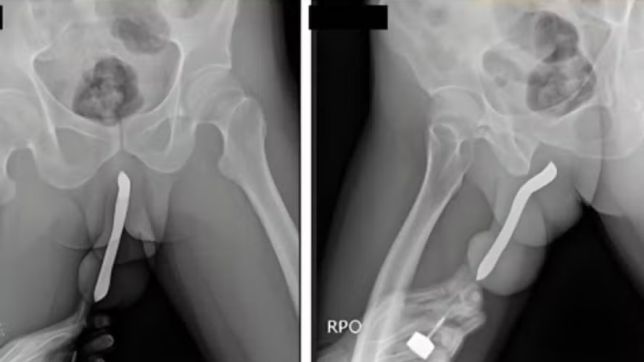

Um número alarmante de pessoas acaba no pronto-socorro todos os anos após inserir objetos nos órgãos sexuais. Seja por curiosidade ou até por fetiches sexuais. O hábito pode ser perigoso e afetar seriamente a saúde.

O site americano Defector analisou os dados mais recentes, referentes a 2024, do banco de dados da Comissão de Segurança de Produtos de Consumo dos EUA que mantém uma lista de visitas ao pronto-socorro e dos motivos que levam as pessoas até lá. Entre eles: os objetos mais frequentes que aparecem presos no ânus das pessoas.